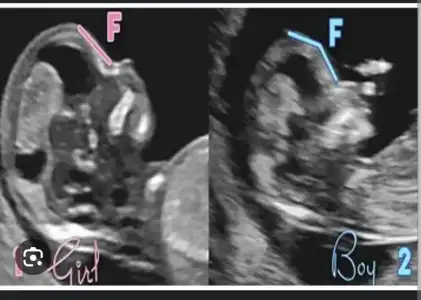

Skull testi de varmış kafatası şekline göre sanırım senin ki erkek oluyor bu teorideTeyzeleri bide bize yorum yapın

Bunu ilk defa duydumSkull testi de varmış kafatası şekline göre sanırım senin ki erkek oluyor bu teoride

Ben de şey duydum mesela kafası biraz daha büyük duruyorsa erkek diyorlar ya da ultrason fotosunda daha toplu duruyorsa erkek, uzunca duruyorsa kızSkull testi de varmış kafatası şekline göre sanırım senin ki erkek oluyor bu teoride

Yok yaa bize eğlence işte ben iki oğlumda da birbirinin tam tersi belirtiler yaşadım birinde ekşi yiyordum birinde tatlı birinde karnım yayikti birinde sivri gibi gibi ama ikiside erkek oldu belirtilerin hiç bir belirleyicigi yok aslındaBen de şey duydum mesela kafası biraz daha büyük duruyorsa erkek diyorlar ya da ultrason fotosunda daha toplu duruyorsa erkek, uzunca duruyorsa kızfasulye seklindeyse kese kız galiba yuvarlaksa erkek mi öyleydi sanırım. Ama tabi bu teoriler değişiyor yani herkeste aynı olmaz ki bence, sağlıkla ve hayırla gelsinler inşAllah

Onu hic bilmiyorumBunu ilk defa duydumkaçıncı haftada bakılıyormuş

ben bunlara da fazla inanmıyorum sağlıklısı olsun diyelimSkull testi de varmış kafatası şekline göre sanırım senin ki erkek oluyor bu teoride